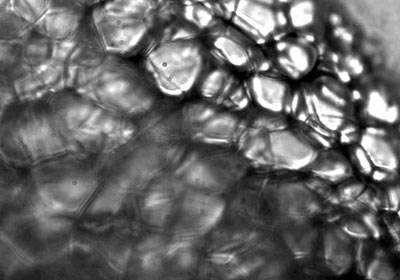

Movie: how it runs , sample: living mice without staining image00